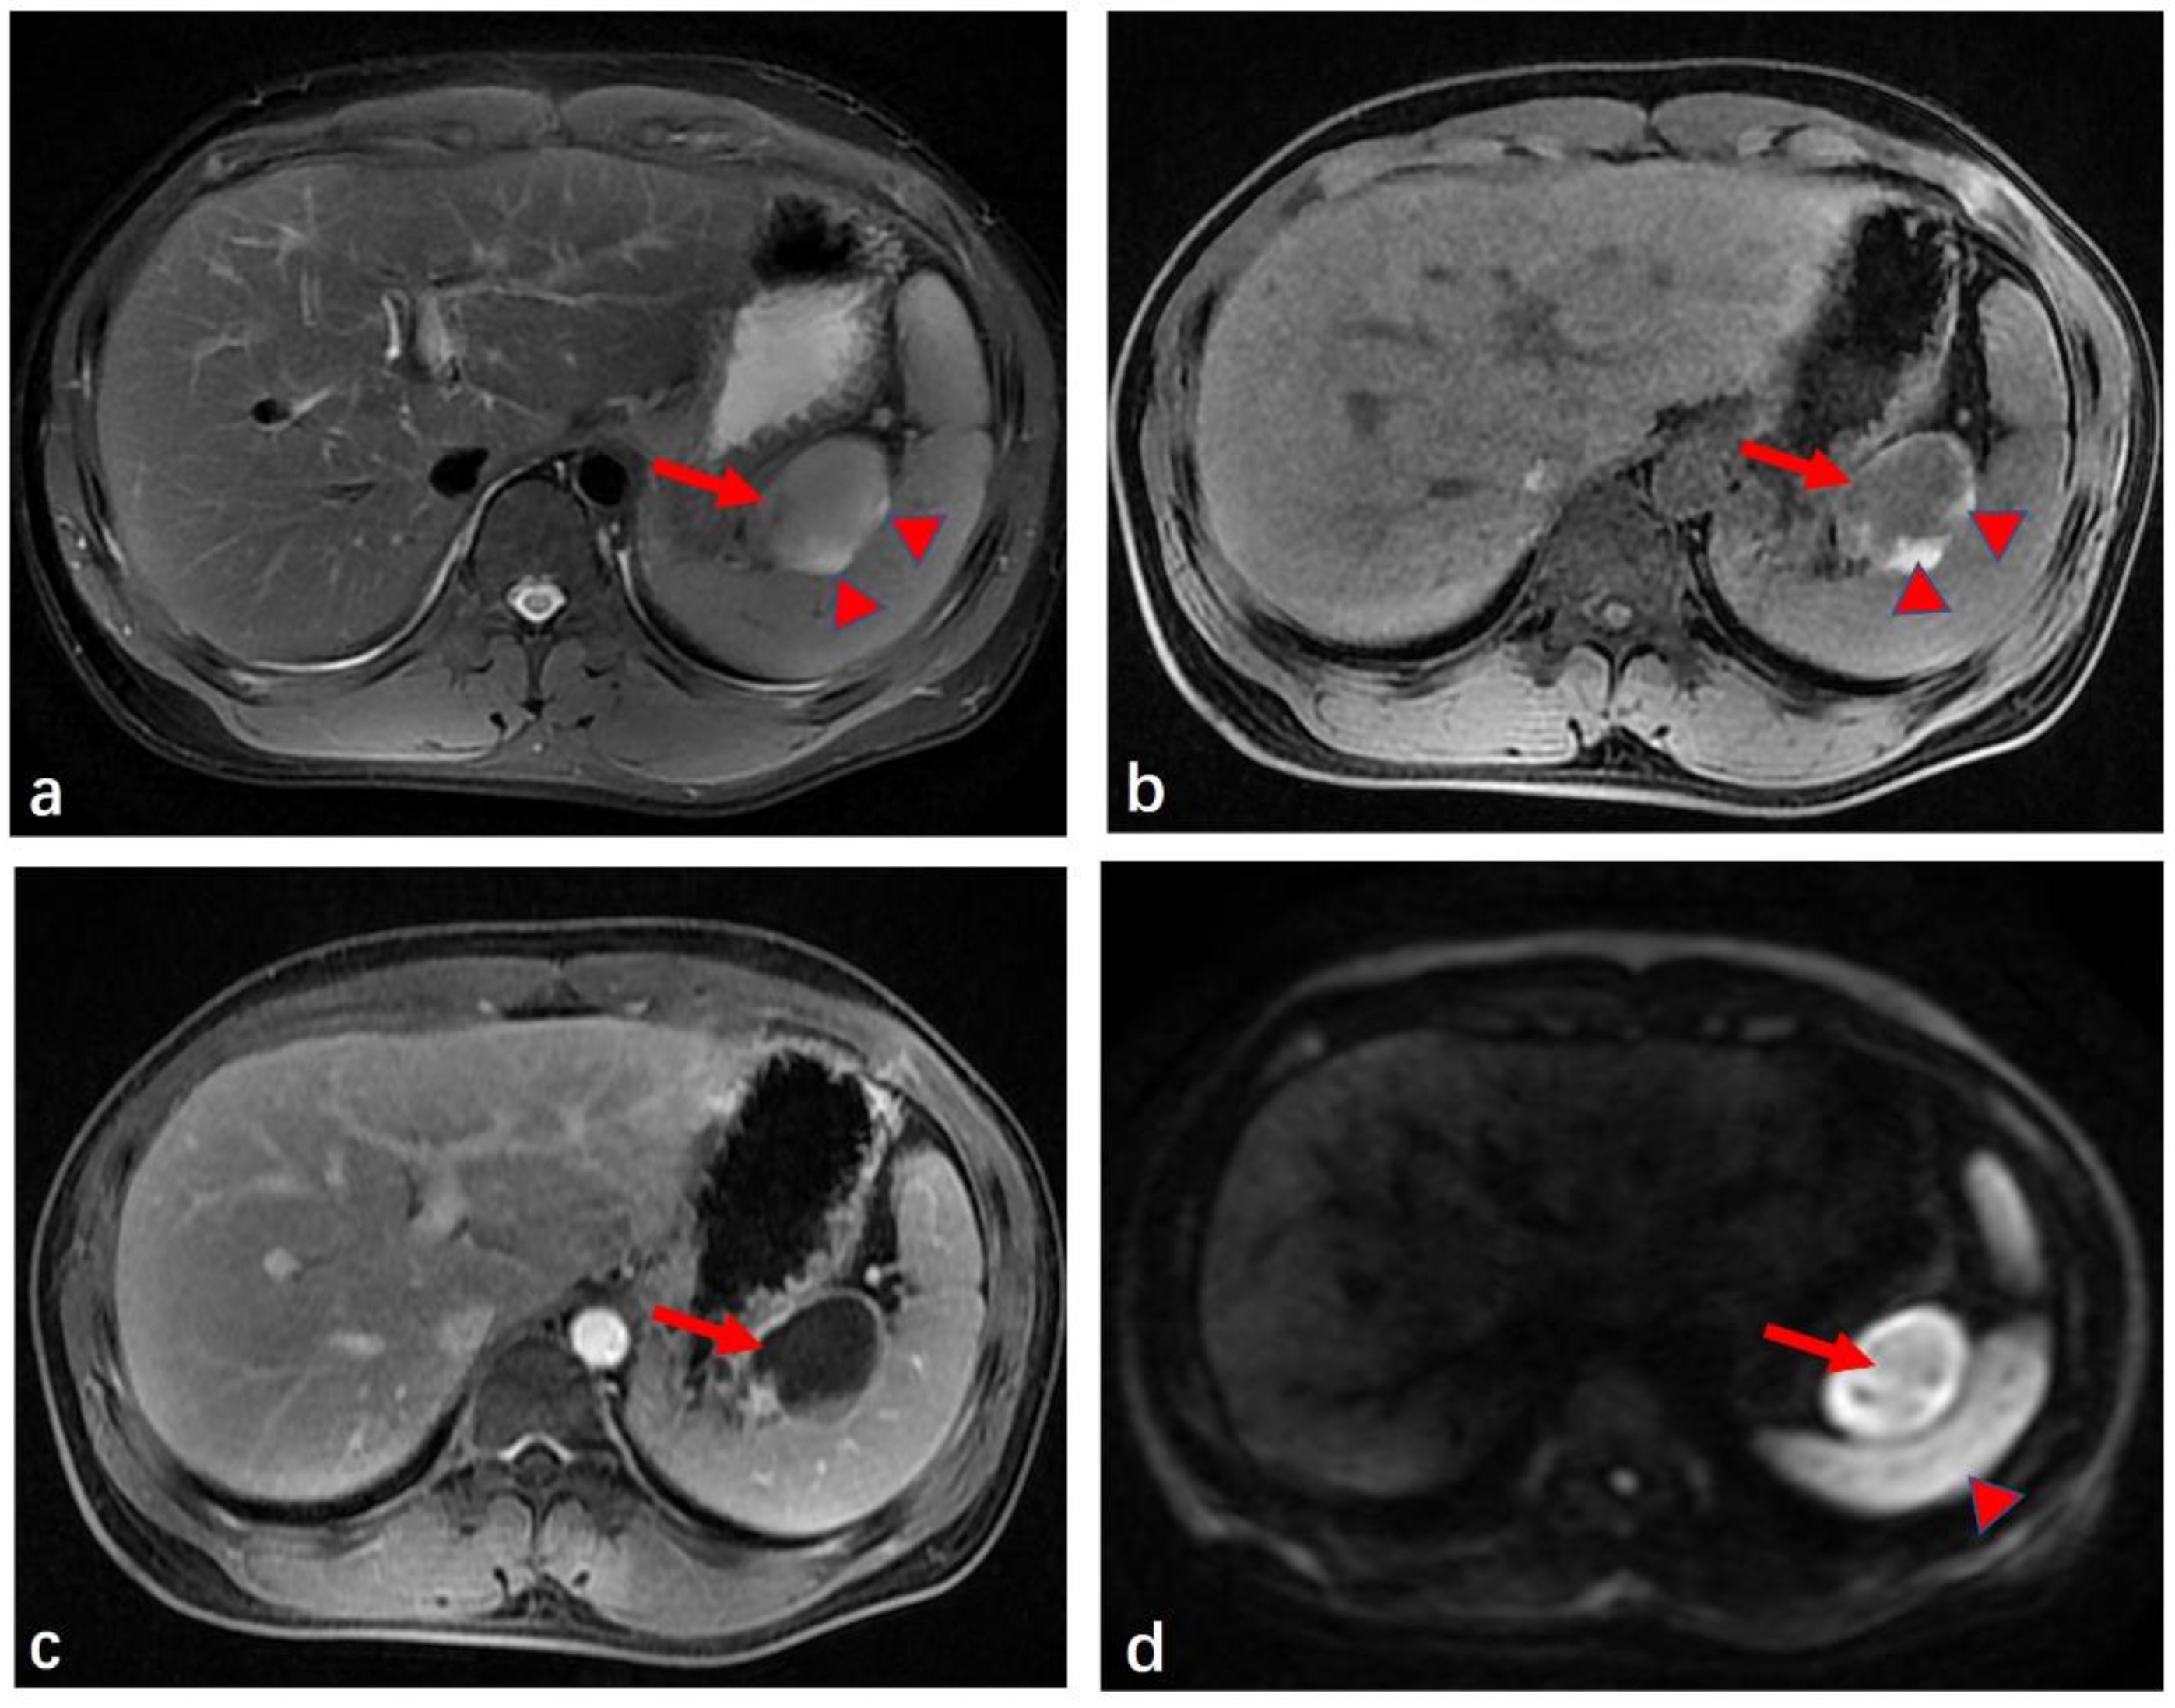

2. Case Presentation